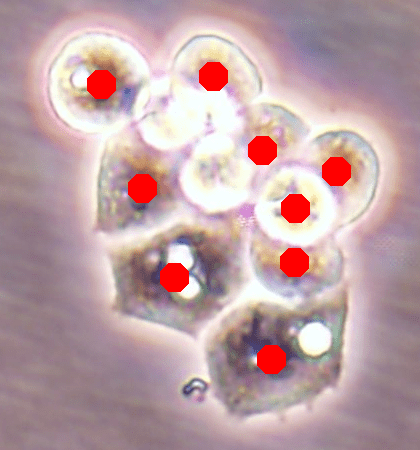

![]() |

| (a) | (b) |

| (c) | (d) |

For an example subimage given in Fig. 2a, these distance definitions are illustrated in Figs. 2b and 2c, respectively. The inner distance definition well indicates the cell centers since it uses the Euclidean distances from pixels to their closest cell centers. However, as it uses the centers as the reference point, the distance decrease from a center to its boundaries is the same for all directions and for all cells. Thus, when it is used alone, this definition imposes a circular and one-sized shape on the cells, as also seen in Fig. 2b. On the contrary, since the normalized outer distance is calculated with a reference to a cell boundary, this decrease may differ from one direction to another as well as from one cell to another, depending on the shape and size of the cell. Thus, it better preserves the morphological characteristics of cells, as seen in Fig. 2c.

The proposed DeepDistance model considers cell detection as a multi-task regression problem that estimates two distance maps from the RGB image, one for formulating the main task of cell detection and the other as an auxiliary task with the motivation of more effectively learning the main task. The FCN architecture given in the previous section is designed to learn these two regression tasks at the same time. This section discusses how this model can be extended to cover more auxiliary tasks, concurrent learning of which may further increase the performance of the main task. For this purpose, this section implements an extended version of the DeepDistance model that comprises an additional task of cell pixel classification. This additional task aims to construct a classification map (as shown in Fig. 2d) from the shared features of the encoder path111To take overlapping cells apart, and hence to obtain an improved map, cell boundaries are widen and subtracted from the classification map. This improved map is also used in the comparison methods to make fair comparisons.. Note that here, instead of defining another regression problem as the additional task, we use a classification problem in order to demonstrate that the model can easily be extended to cover the auxiliary tasks related with regression as well as classification.